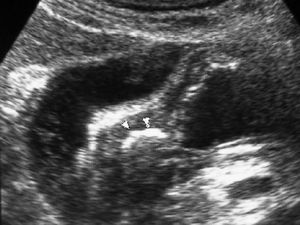

Fig. 4--Perforación duodenal por espina de pescado. (A) Ecografía donde se observa una estructura lineal hiperecogénica (flechas) que sale del duodeno (D). (B) En el estudio de tomografía computarizada se identifica como material hiperdenso (flecha) que corresponde a la espina de pescado, con reacción de la grasa adyacente (puntas de flecha) y líquido en espacio pararrenal anterior derecho.